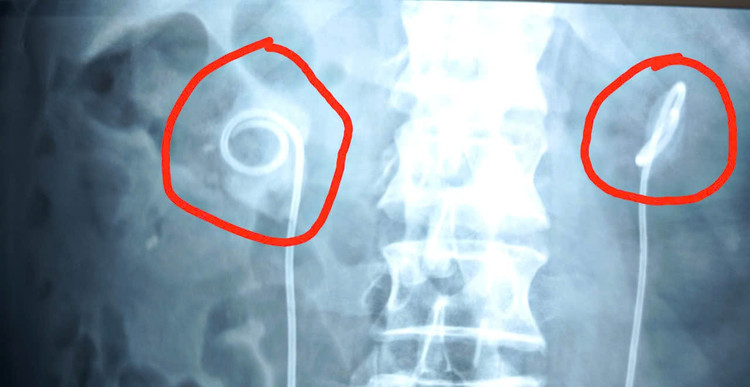

Trước đó 2 năm, ông T. được chẩn đoán mắc ung thư bàng quang, đã mổ cắt bàng quang toàn bộ và được đưa 2 đường niệu quản qua da. Sau mổ, ông T được đặt sonde JJ (hay còn gọi là ống thông JJ, ống thông niệu quản đôi chữ J- là một loại ống thông mềm, hình cong ở hai đầu giống chữ J) từ bể thận xuống niệu quản để dẫn lưu nước tiểu ra ngoài, trong thời gian chờ niệu quản hồi phục tổn thương.

Theo chỉ định, sonde JJ cần được rút ra trong vòng 3 tháng. Tuy nhiên, ông T. không đi tái khám để rút sonde vì cho rằng sức khỏe bình thường, dù được bác sĩ và gia đình nhắc nhở nhiều lần.

Khoảng 2 tuần gần đây, ông T cảm thấy người mệt mỏi, sốt nhẹ và phát hiện một mảnh sonde JJ bị mục gãy, đào thải ra ngoài túi hậu môn nhân tạo hứng nước tiểu. Hoảng hốt, ông mới đến bệnh viện kiểm tra.

“Qua thăm khám, chúng tôi không thể rút sonde JJ bằng biện pháp thông thường. Do thời gian lưu sonde quá lâu, bệnh nhân được chỉ định chụp CT. Kết quả cho thấy sỏi bám vòng quanh sonde JJ chiếm gần như hết diện tích đài bể thận 2 bên. Thận phải có viên sỏi lớn 34x29mm, thận trái 20x13mm kèm nhiều viên nhỏ rải rác. Sỏi ở trên thận gây ứ nước thận độ 3.